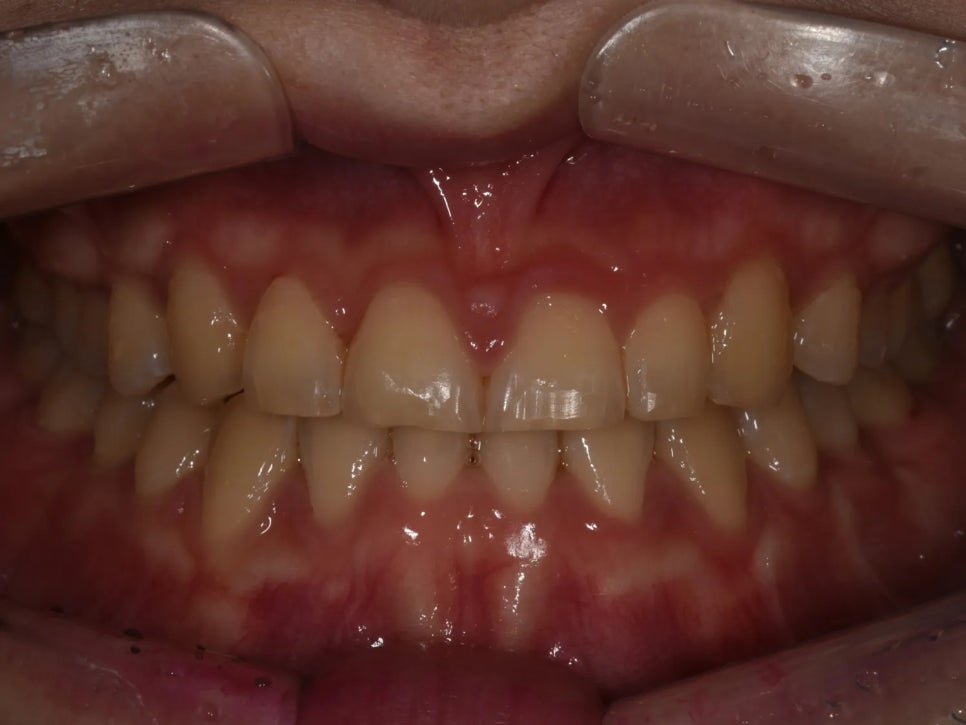

치료 결과 – 반대교합 해소 및 정상 교합 확립

치료가 마무리된 후의 모습입니다. 반대교합이 완전히 해소되어 정상적인 교합 관계가 확립되었어요!

치료가 완료된 모습. 정상교합을 회복했습니다.

치료 완료 – 반대교합이 해소되고, 아래 치열의 공간도 깔끔하게 정리된 모습

치료 전후를 비교하면 변화가 확연하지 않나요?

안쪽으로 들어가 있던 두 번째 앞니도 제자리를 찾았고, 아래 치열의 불필요한 공간도 모두 정리되었습니다. 기능적 안정성과 심미성 모두를 확보한 결과라고 할 수 있어요.